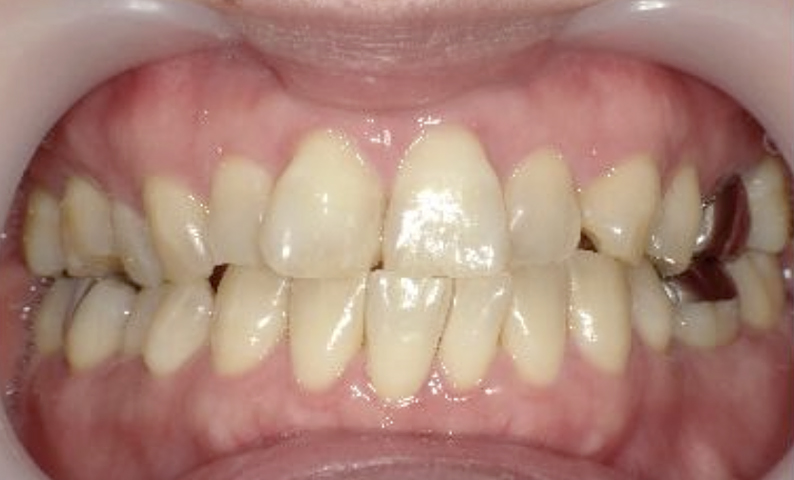

症例_003 下顎だけの部分矯正

治療期間:10ヶ月金額:24万円+税女性前歯のガタガタ下の前歯だけ上顎は補綴治療中